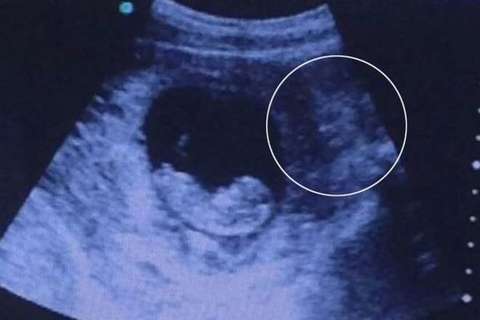

Per i sanitari si tratta di un caso di "morte intrauterina che in Italia ha percentuali tra il 4 e il 5%". Sul caso indagano i carabinieri. Disposta l'autopsia sul feto

La foto è stata oggetto di centinaia di migliaia di visualizzazioni. Spesso, come riporta anche il Mirror, che dalle ecografie spuntano immagini a volte inquietanti

È arrivata in ospedale mercoledì notte con febbre alta e sintomi di gastroenterite. Giovedì mattina i medici hanno deciso di iniziare il parto cesareo ma il feto era già morto